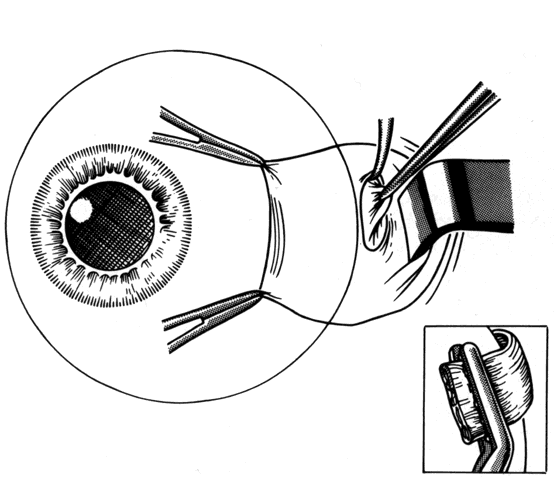

PERSISTENT UNSATISFACTORY ALIGNMENT

Persistent unsatisfactory alignment may be a complication. Use of adjustable sutures reduces the frequency of this complication. We prefer to perform suture adjustment in the operating room. To do this, we use a perimuscular anesthetic combined with short-acting intravenous sedation (Fig. 45). After the muscles have been temporarily tied into position, sedation is withdrawn. The patient can sit up and assist the surgeon in determining the position of the muscles before permanent knots are tied. Short-acting general anesthesia with agents such as propofol may also be used to achieve rapid recovery of consciousness so that adjustment may be performed in the recovery area.

Fig. 45. Suture adjustment can be accomplished intraoperatively if perimuscular anesthesia is combined with short-acting intravenous sedation. After sedation is withdrawn, the patient will become alert. The patient is seated, and glasses are used when needed. Cover testing is performed with use of an eye chart for fixation. The position of the muscle is adjusted until the ocular alignment is satisfactory.